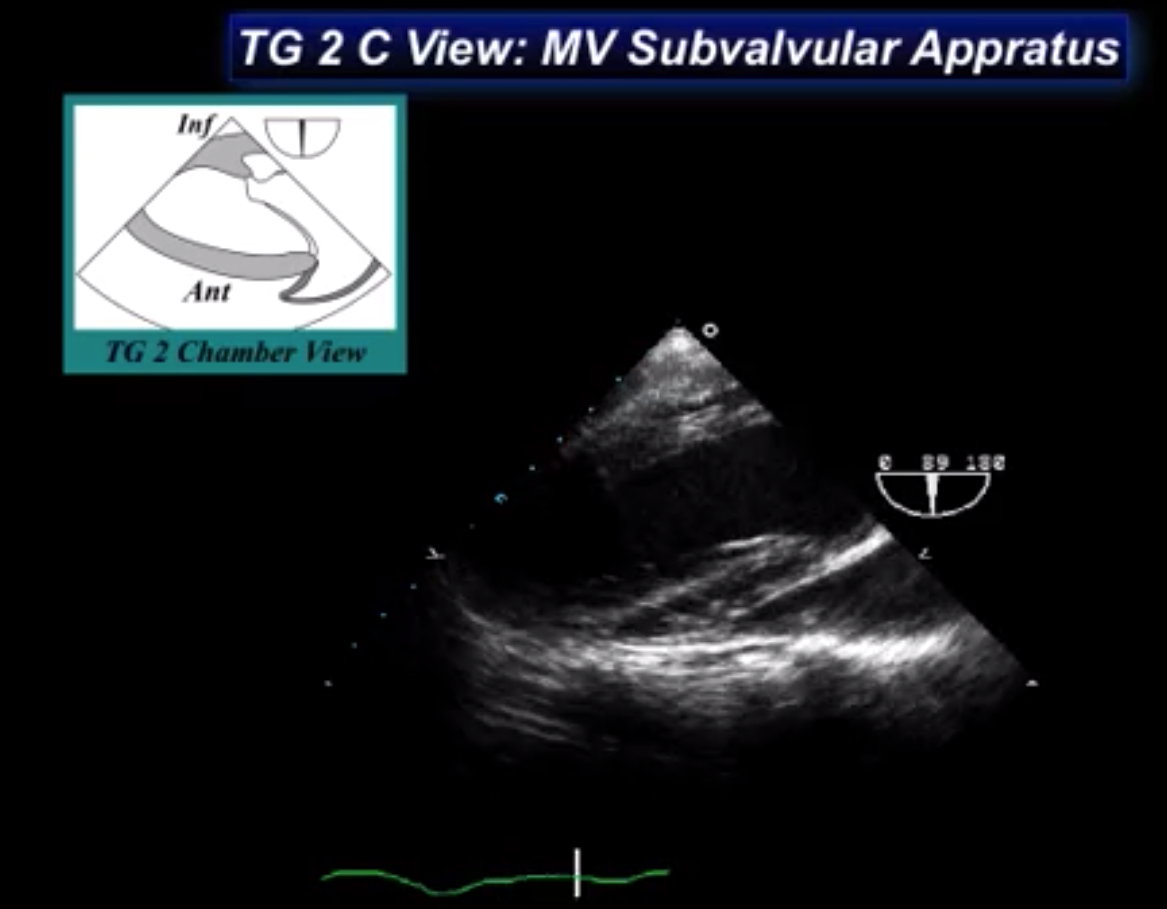

What view is seen here?

Transgastric 2 chamber view

Mitral Valve Subvalvular Apparatus

What walls of the heart are shown here?

INFERIOR = CLOSE TO THE PROBE

ANTERIOR = AWAY FROM THE PROBE